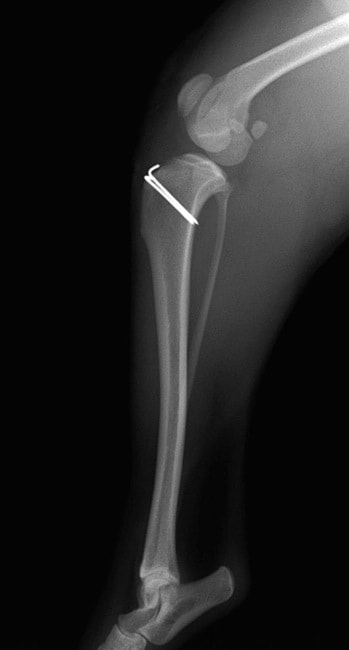

■ 症例24 キャバリア 7か月

左右膝蓋骨内方脱臼(左:グレードⅣ 右:グレードⅢ)

以前から左右後肢の跛行が認められ、整形外科学的検査・レントゲン検査により左右の膝蓋骨脱臼が認められた。症状が重度である左膝の膝蓋骨脱臼整復術を行った。外科手技は縫工筋及び内側広筋の解放、脛骨粗面の外側転位、滑車ブロック形造溝術、内外側関節方の縫縮を実施した。術後一か月時点で、左の膝蓋骨は安定しており経過は良好である。

本症例は成長期における重度の膝蓋骨脱臼であり、術後の再発の可能性もあるため、経過をしっかりと観察していく必要がある。また、今回手術を実施していない右膝に関しても経過を観察し、手術を検討していくこととする。